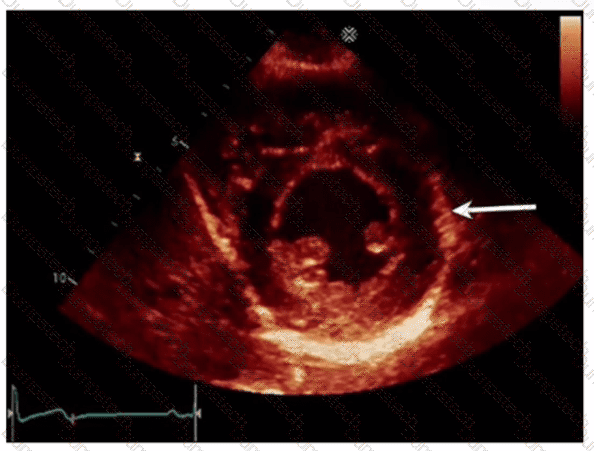

Which left ventricular regional wall segment is indicated by the arrow on this image?

Question # 4

Options:

A.

Anterior

B.

Anterolateral

C.

Inferior

D.

Inferolateral